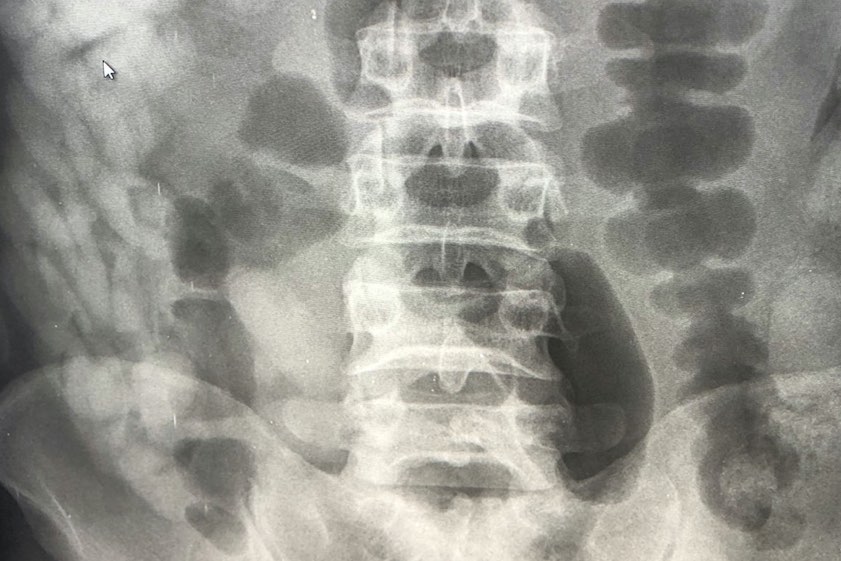

"Das Röntgenbild bestätigte den Verdacht der Zöllner. Im Laufe des Tages kamen 97 Behältnisse mit Kokain zum Vorschein, die über den natürlichen Weg ausgeschieden wurden", berichtete heute Marie Müller, die Pressesprecherin des Hauptzollamts München. Insgesamt sei rund ein Kilo Kokain sichergestellt worden. Gegen den Mann sei auf Antrag der Staatsanwaltschaft ein Haftbefehl erlassen worden. Die weiteren Ermittlungen habe das Zollfahndungsamt München übernommen.